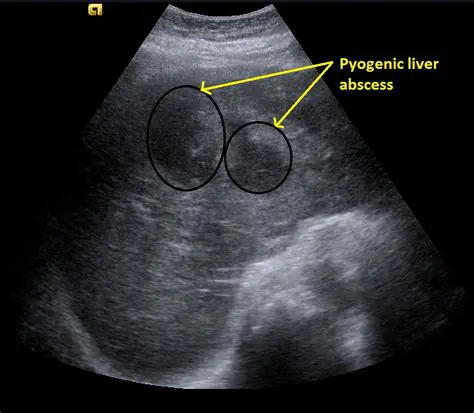

Ultrasound Diagnosis of Liver Abscess